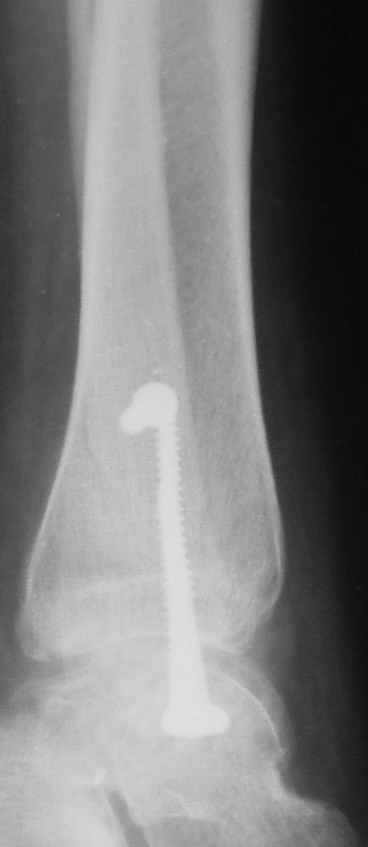

Ниже рентгенограммы

До операции 28 июля

Риторический вопрос - в каком руководстве рекомендован такой способ остеосинтеза наружной лодыжки?

Очевидно, такой результат операции был запрограммирован. При невосстановленной длине и практически нефиксированной малоберцовой кости (этот кортикальный винт - как карандаш в стакане), при неустраненном подвывихе, невправленной и тоже нефиксированной внутренней лодыжке нет стабильной вилки сустава. Если такую операцию сделать даже сразу, а не через 4 месяца, то результат ожидаем

тот же.

Вообще говоря, такое повреждение вполне успешно можно лечить без операции - если 6 недель подержать в гипсовом "сапожке" с хорошо устраненным подвывихом. Вероятное несращение внутренней лодыжки не обязательно компрометирует результат.

Ну а уж если выбран остеосинтез - нначать надо было с репозиции малоберцовой кости с точным восстановлением длины, с фиксацией треть-трубчатой пластиной по задней поверхности. Позиционный винт

избыточен - повреждение практически подсиндесмозное. А если бы

действительно было повреждение синдесмоза - в 4 месяца позиционный винт - не решение. Внутренню лодыжку такую - надо было бы спицами и проволочной петлей. Извините за эти банальности.